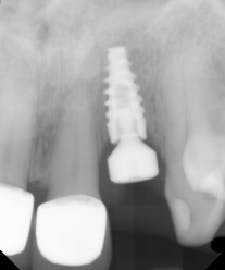

The patient presented to restore the implant six months later with a predicted large vertical and horizontal tissue defect (figure 3). The implant was restored with gingival ceramics to compensate for the ridge defect (figure 4).

The patient was very pleased with the final outcome (figure 5), even though this case certainly would not be considered an esthetic success. Because of the patient’s concerns and low smile line (figure 6), this case was completed six months postextraction and in a cost-efficient manner.